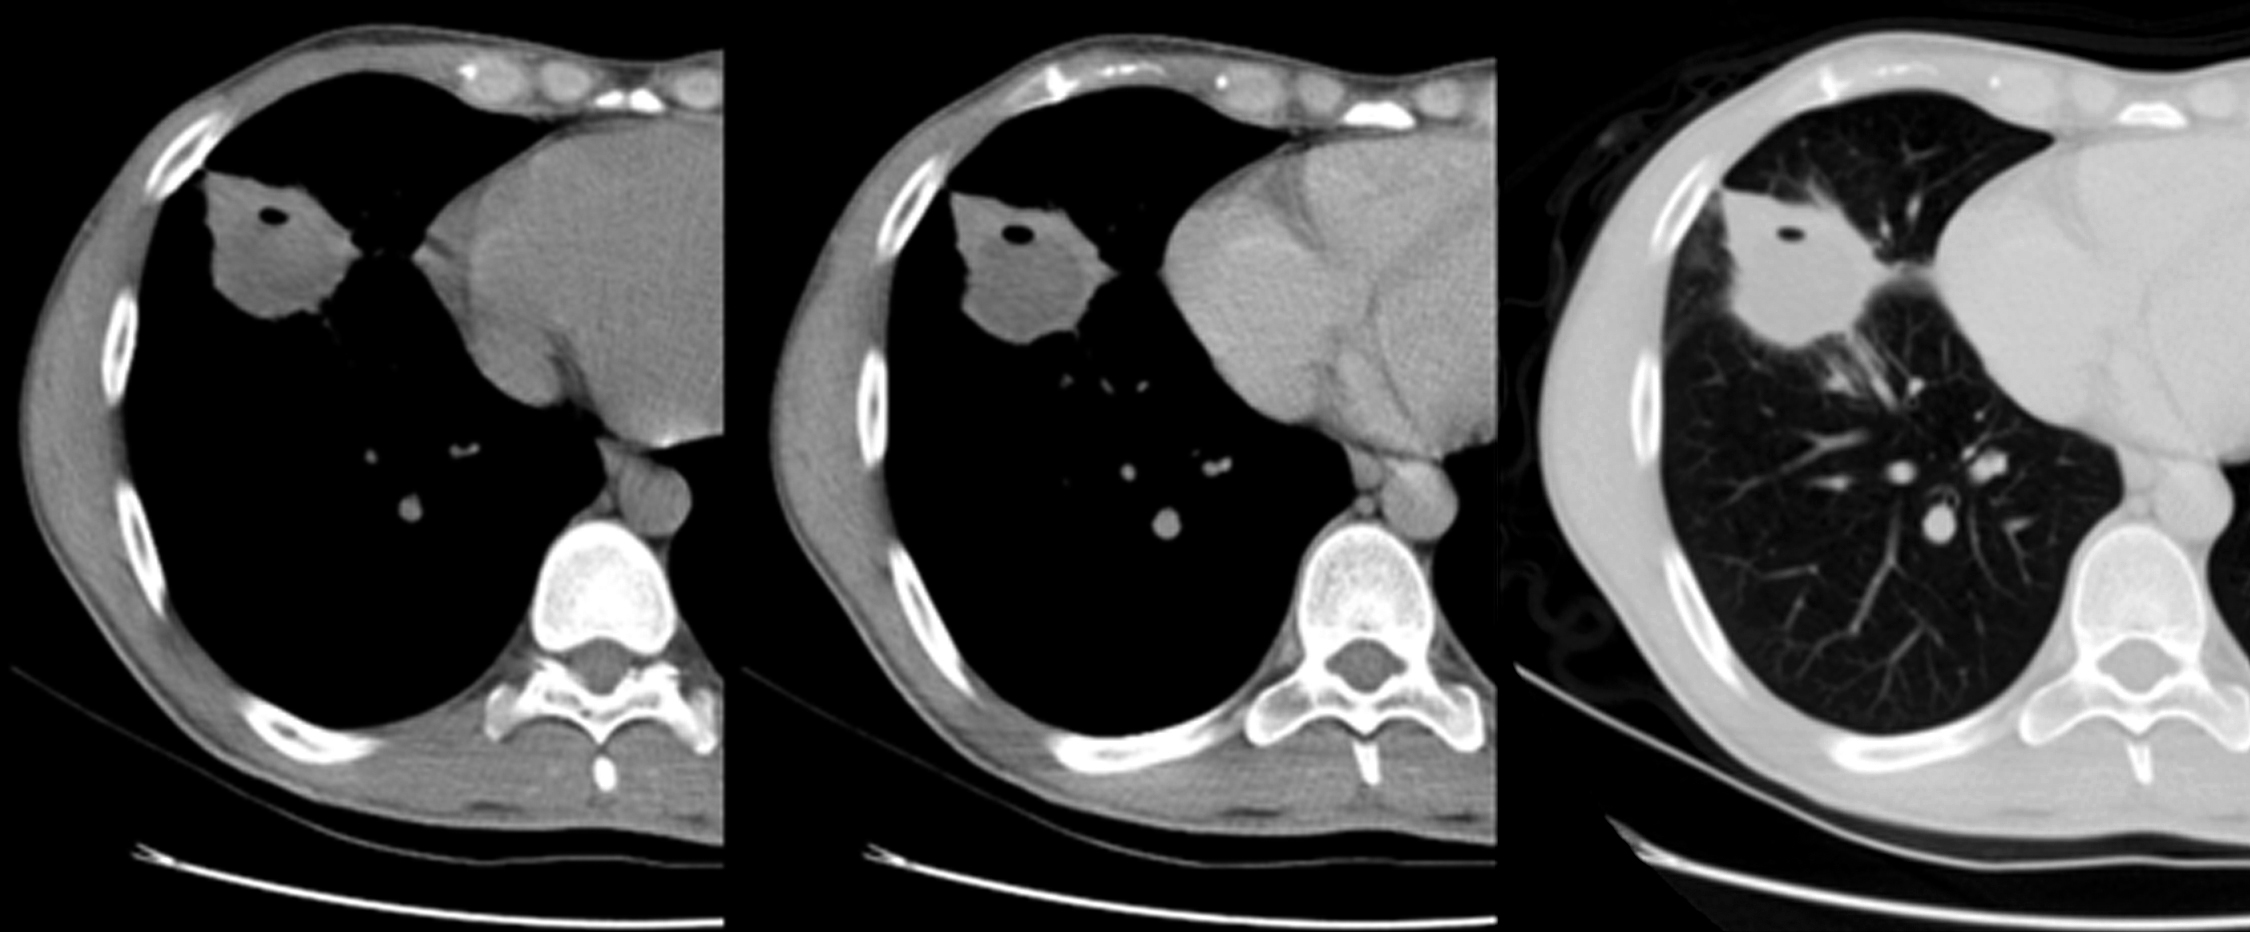

Se solicita RM, que se realiza en condiciones basales y tras la administración de gadolinio. Se observa tumoración sólida de igual tamaño y características que en TC previas, que impresiona de origen mesentérica o peritoneal y cambia de posición en estudios sucesivos, actualmente localizándose en flanco izquierdo. (Figura 8)

Figura 8

RM de abdomen: secuencia T2 coronal (a); secuencia T2 axial (b); secuencia ponderada en T1 axial (c); secuencia ponderada en T1 axial con contraste (d). Masa sólida del mismo tamaño y características que en las TC anteriores (flechas).

La apariencia de TC del TIM abdominal es variable. La masa puede ser hipo o isodensa en relación al músculo en exploraciones sin contraste y se han observado calcificaciones en casos en páncreas, estómago e hígado. Tras la administración de medio de contraste generalmente hay realce pero no es muy pronunciado. Se han observado variedad de patrones que incluyen desde la ausencia de realce, realce periférico temprano con relleno central tardío, realce heterogéneo y realce homogéneo. Las lesiones más grandes pueden tener necrosis central (1, 4, 12, 14, 15). En las imágenes de RM, la apariencia de estos tumores también es variable. Generalmente son hipointensos en relación al músculo en imágenes potenciadas en T1, hiperintensas en imágenes potenciadas en T2 y con realce heterogéneo después de la administración de medio de contraste. (1, 4, 12, 15)